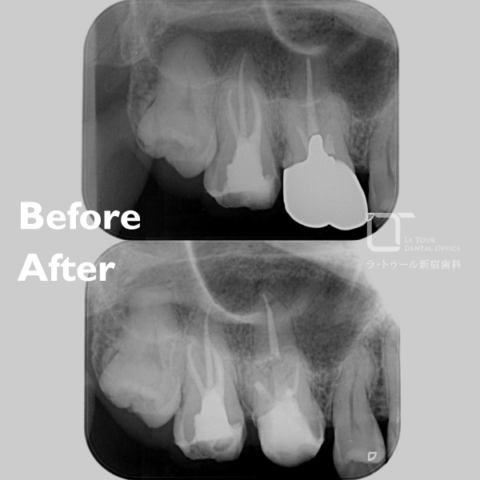

セラミック治療の治療例です。虫歯になった歯を、見た目もきれいに治したいとのご希望で来院されました。当院にて、3本同時にセラミックによる修復を実施しました。染め出しにより取り残しや汚れを確認し、プラークなどを除去したうえでセラミックを装着しています。オキシガードは、過酸化物と還元剤による化学重合反応により、歯科接着用レジンセメント表面の未重合層を硬化させる材料です。さらに、未重合層を空気から遮断することで確実な硬化を促します。接着効率をあげるためにラバーダムを使用し治療を行っております。

術前から術後までの治療の流れ

虫歯処置後

セット後